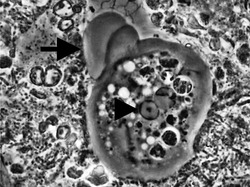

Entamoeba cells are small, with a single nucleus and typically a single lobose pseudopod taking the form of a clear anterior bulge. They have a simple life cycle. The trophozoite (feeding-dividing form) is approximately 10-20 μm in diameter and feeds primarily on bacteria. It divides by simple binary fission to form two smaller daughter cells. Almost all species form cysts, the stage involved in transmission (the exception is Entamoeba gingivalis). Depending on the species, these can have one, four or eight nuclei and are variable in size; these characteristics help in species identification.

Uninucleated trophozoites convert into cysts in a process called encystation. The number of nuclei in the cyst varies from 1 to 8 among species and is one of the characteristics used to tell species apart. Of the species already mentioned, Entamoeba coli forms cysts with 8 nuclei while the others form tetra-nucleated cysts. Since E. histolytica does not form cysts in vitro in the absence of bacteria, it is not possible to study the differentiation process in detail in that species. Instead the differentiation process is studied using E. invadens, a reptilian parasite that causes a very similar disease to E. histolytica and which can be induced to encyst in vitro. Until recently there was no genetic transfection vector available for this organism and detailed study at the cellular level was not possible. However, recently a transfection vector was developed and the transfection conditions for E. invadens were optimised which should enhance the research possibilities at the molecular level of the differentiation process.[10][11]